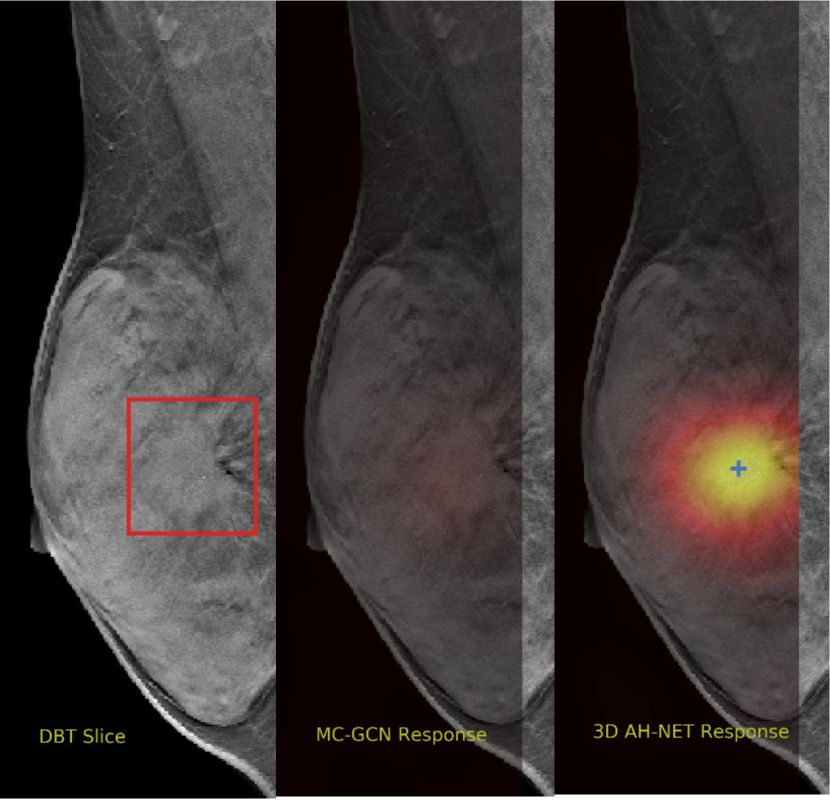

Refer to caption

Figure 5: The visual comparisons of the network responses on 2 different DBT volumes from 2D GCN and the 3D AH-Net with the encoder weights transferred from it. Each volume is visualized with the maximum intensity projection of the xy𝑥𝑦xy plane (top-left), the xz𝑥𝑧xz plane (bottom) and the yz𝑦𝑧yz plane (right). The ground truth lesion centres are shown on the left. With the additional AH-Net Decoders, 3D AH-Net could effectively detect the missing lesion in the first volume (upper row) and remove the false positives in the second volume (lower row).

Non-maximal suppression is performed on the network output map to obtain the lesion locations. The network responses at the local maximal voxels are considered as the confidence scores of the cancerous findings. Fig. 5 shows some visual comparison of the networks output.

We selected some example slices from the DBT dataset to demonstrate the advantage of our proposed AH-Net for the Breast cancer screening. From Fig. 8 to Fig. 12, we show slices from five test DBT volumes that both the MC-GCN and the proposed 3D AH-Net could successfully detect the suspected breast lesion. The original DBT slice is shown on the left with the lesion annotated by our radiologist. Please note the original annotation is a 3D box. The figures in the middle and on the right are response maps from MC-GCN and 3D AH-Net overlaid on the original image, respectively. The detection locations obtained with non-maximal suppression are displayed with cross markers. As shown in the images, the proposed network can detect breast lesions varying in sizes and appearances. The confidence of the 3D AH-Net is usually higher than that of MC-GCN. From Fig. 13 to Fig. 17, we show five volumes that MC-GCN failed to detect the lesions since the lesions were not distinguishable from other breast tissues using the information within the slice. In contrast, 3D AH-Net was able to detect the lesions from such volumes using the 3D context between slices. As shown in Fig. 18 to Fig. 22, there are also volumes with lesions that both network failed to detect. Such lesions normally reside in the dense breast tissues. The boundary between these lesions and the normal breast tissues usually have low contrast. The networks sometimes also confuse them with other roundish structures in the breast such as lymph nodes or skin moles.

Figure 13: Example DBT slice 6 with a lesion that can only be detected by 3D AH-Net. The lesion is highly blended within the dense breast tissues which makes it challenging for both the radiologists and the networks to detect through a single slice. In contrast, the lesion can be detected by considering the consistency of the structure across a few neighbouring slices.